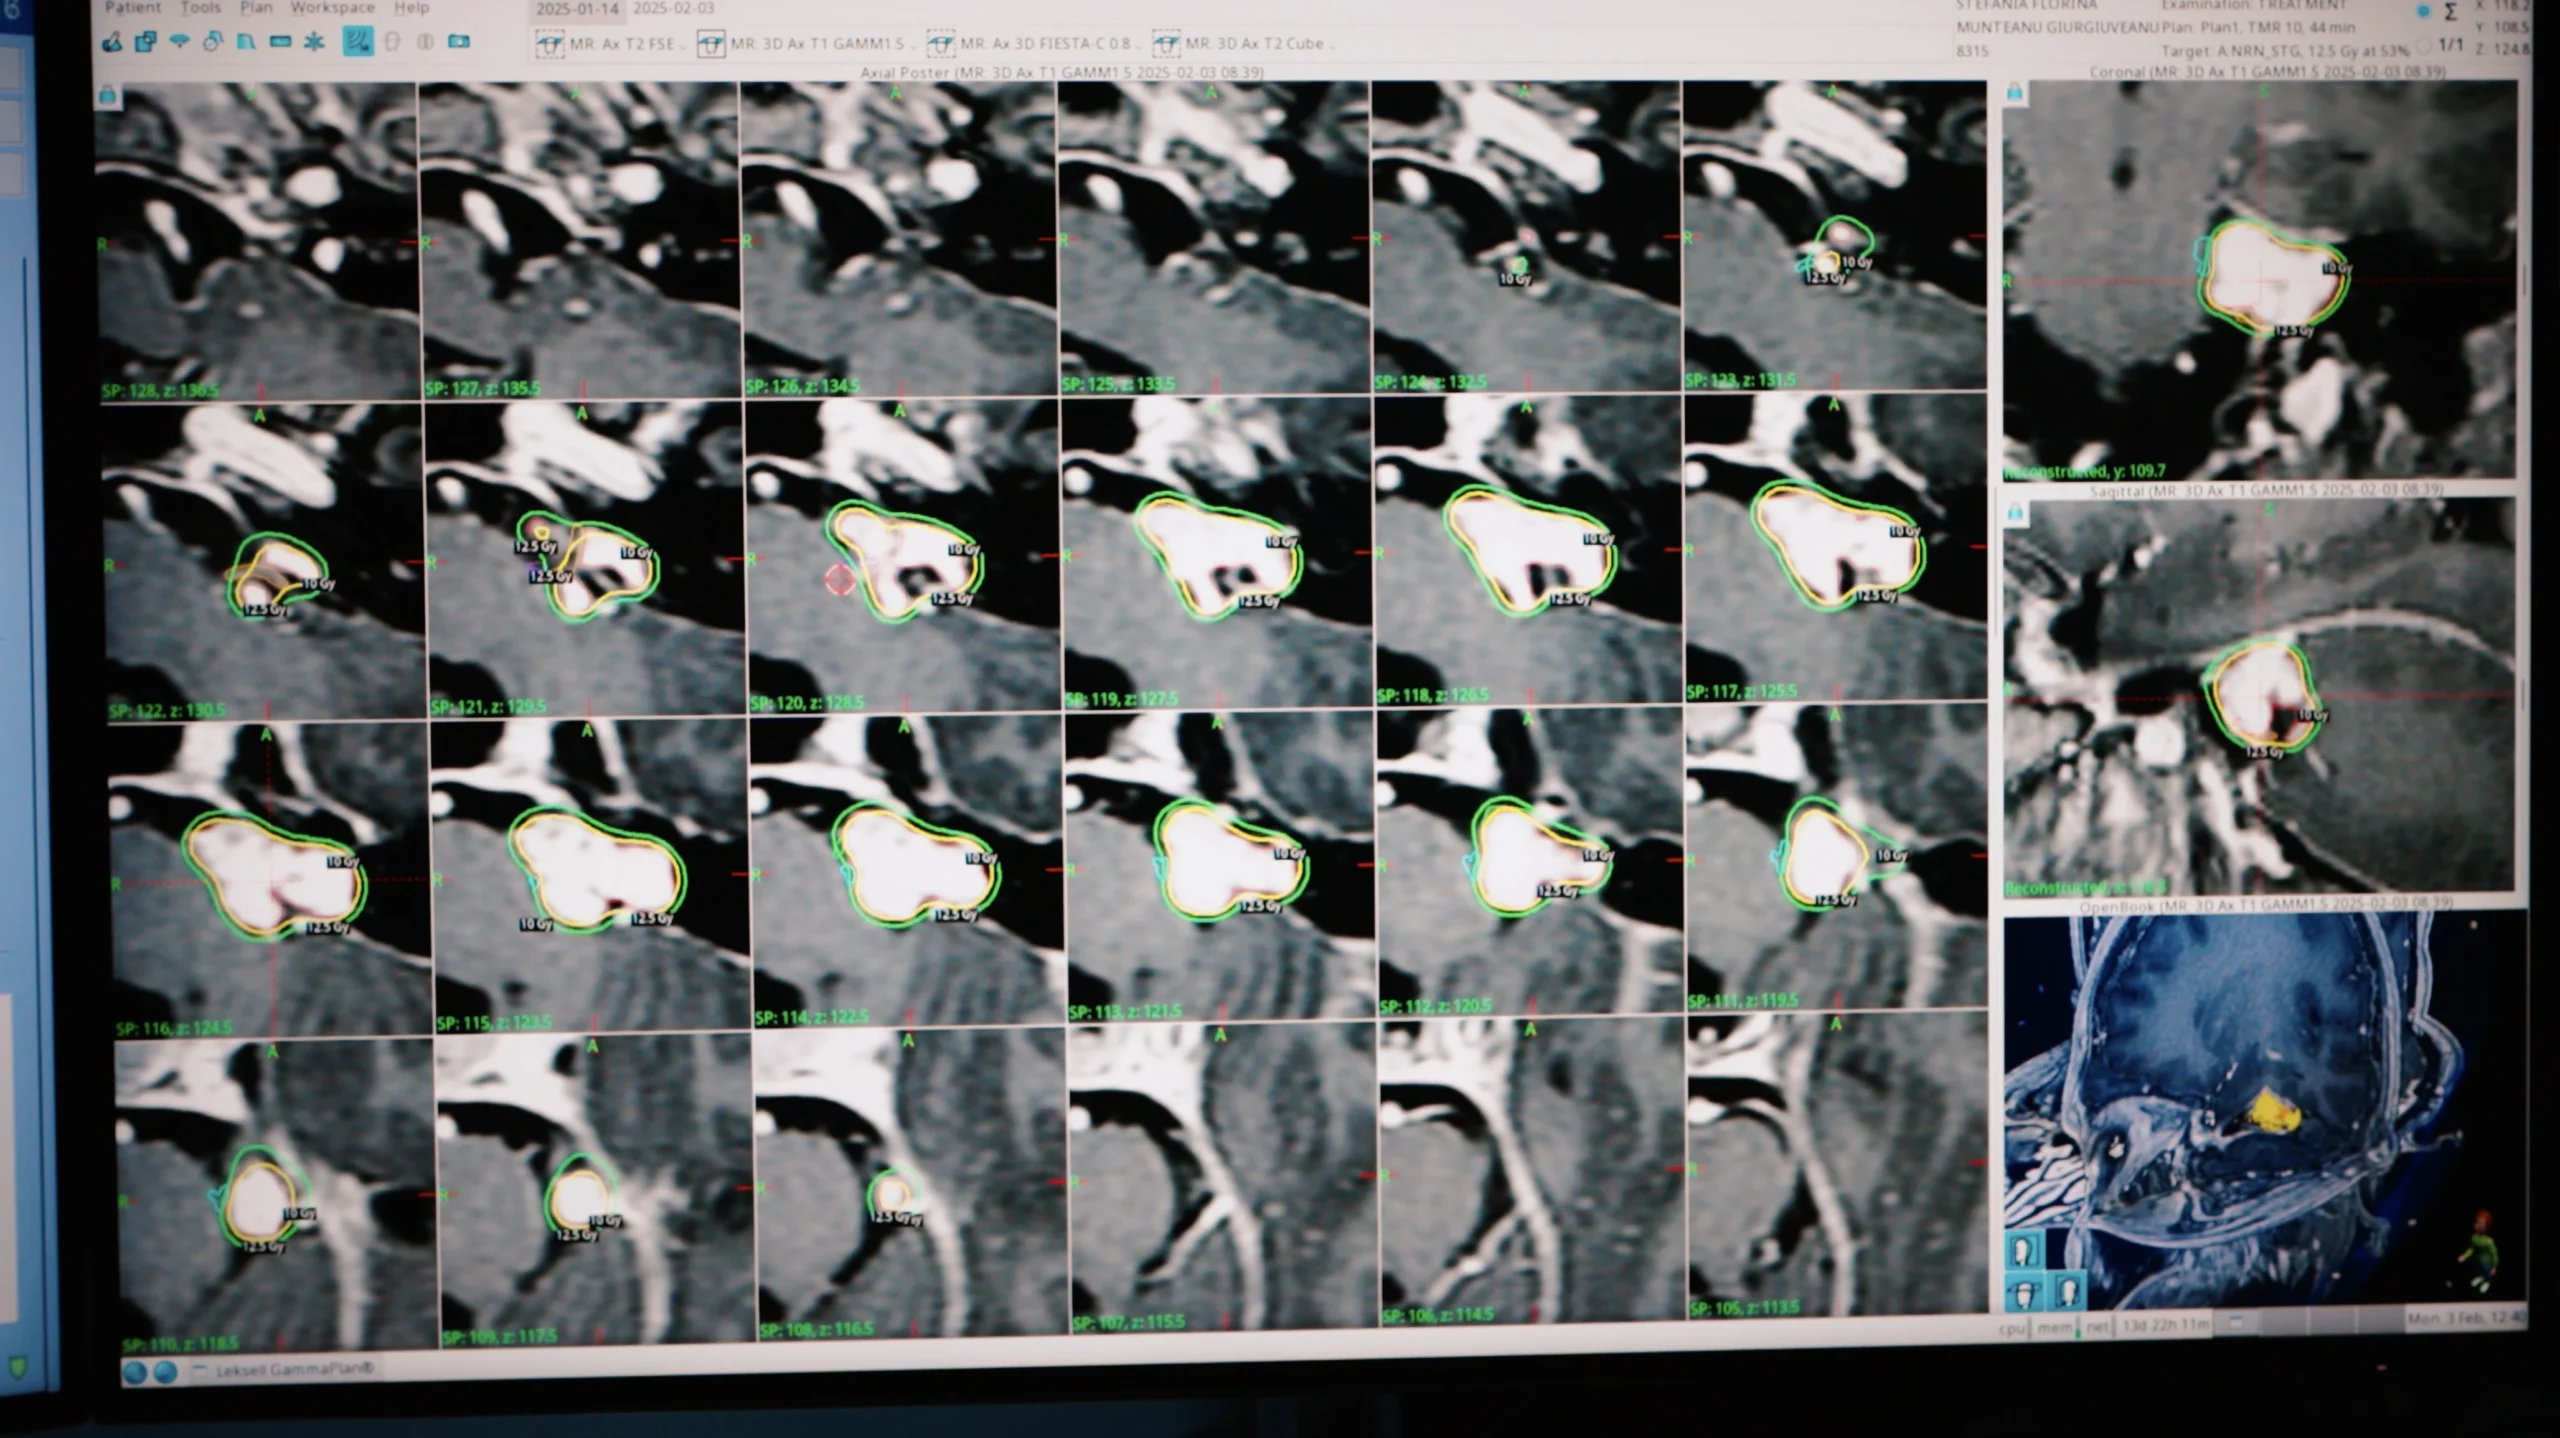

Furnizăm echipamente medicale avansate, selectate pentru performanță, siguranță și fiabilitate în domenii critice precum oncologia, radioterapia și neurochirurgia.